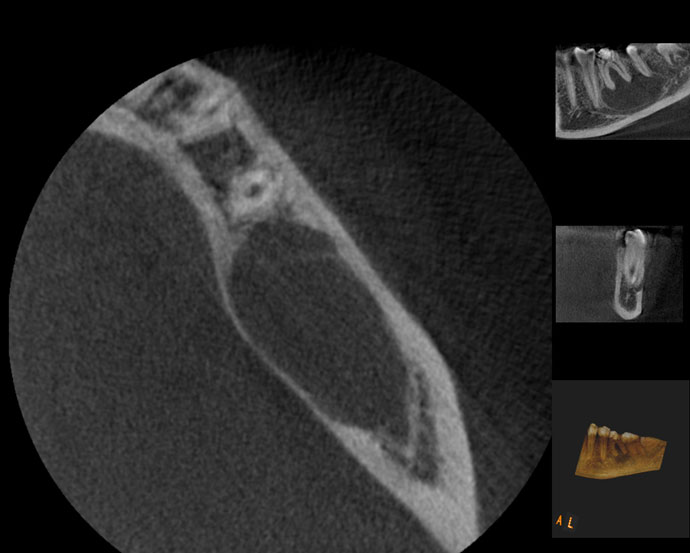

Naso-Palatine Cyst misdiagnosed + Calcified Canal + Broken Instrument

• This was a Naso-palatine cyst mis-diagnosed as a lesion of endodontic origin

• Treatment was started by the previous clinician and referred to our clinic.

• Referred for:

a) removal of broken instrument in the left maxillary central incisor

b) Location of calcified canal in the right maxillary central incisor

Pre-op

Calcified canal (Red arrow), Broken instrument (Yellow arrow)

Right Maxillary incisor: CBCT shows that canal is under the palatal wall of the access cavity.

Canal located

Right maxillary incisor cleaned, shaped and obturated.

Fractured instrument in the left maxillary incisor.

Fractured instrument by-passed

Pre-op & Post-op

Courtesy: Dr. Anjan Shah, Oral surgeon